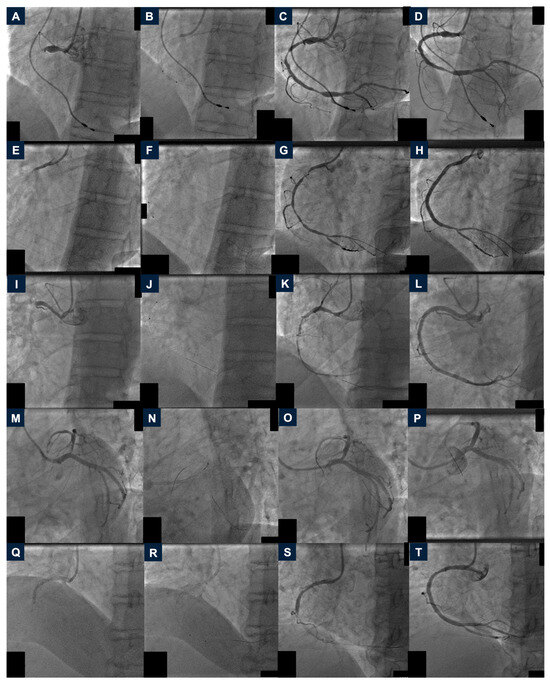

2.2. Case 2

2.3. Case 3

2.4. Case 4

2.5. Case 5

2.6. Case 6

3. Discussion